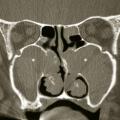

Rhinosinusites chroniques de l’adulte : nouvelle définition, nouveau diagnostic

La rhinosinusite chronique occupe une place centrale en pathologie rhinologique de l’adulte. Ce terme de « rhinosinusite chronique » a longtemps fait l’unanimité chez les rhinologistes qui se fondaient : sur l’unicité apparente de la muqueuse respiratoire du nez ; sur une communauté d’origine de l’ethmoïde et des…